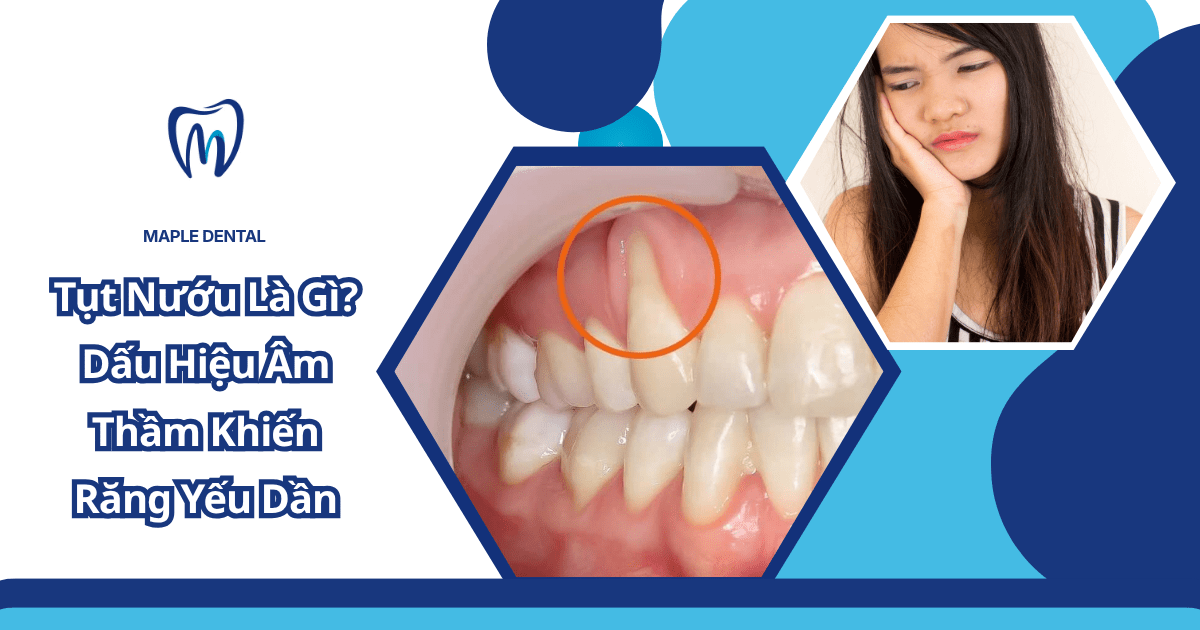

Tụt nướu là tình trạng nướu co rút xuống khỏi vị trí bình thường, làm lộ chân răng và khiến răng dễ ê buốt hơn khi ăn uống. Đây là vấn đề răng miệng khá phổ biến nhưng thường bị bỏ qua vì tiến triển âm thầm. Nếu không được phát hiện sớm, tình trạng này có thể khiến răng yếu dần, mất thẩm mỹ và tăng nguy cơ viêm nha chu.

Tụt nướu (tụt lợi) là tình trạng mô nướu co rút xuống khỏi vị trí ban đầu, làm lộ phần chân răng. Khi nướu không còn bao phủ đầy đủ, răng mất đi lớp bảo vệ tự nhiên, trở nên nhạy cảm và dễ tổn thương.

Tình trạng này có thể xảy ra ở một hoặc nhiều răng và tiến triển theo thời gian nếu không được kiểm soát.

- Răng có cảm giác dài hơn so với trước đây

- Lộ phần chân răng